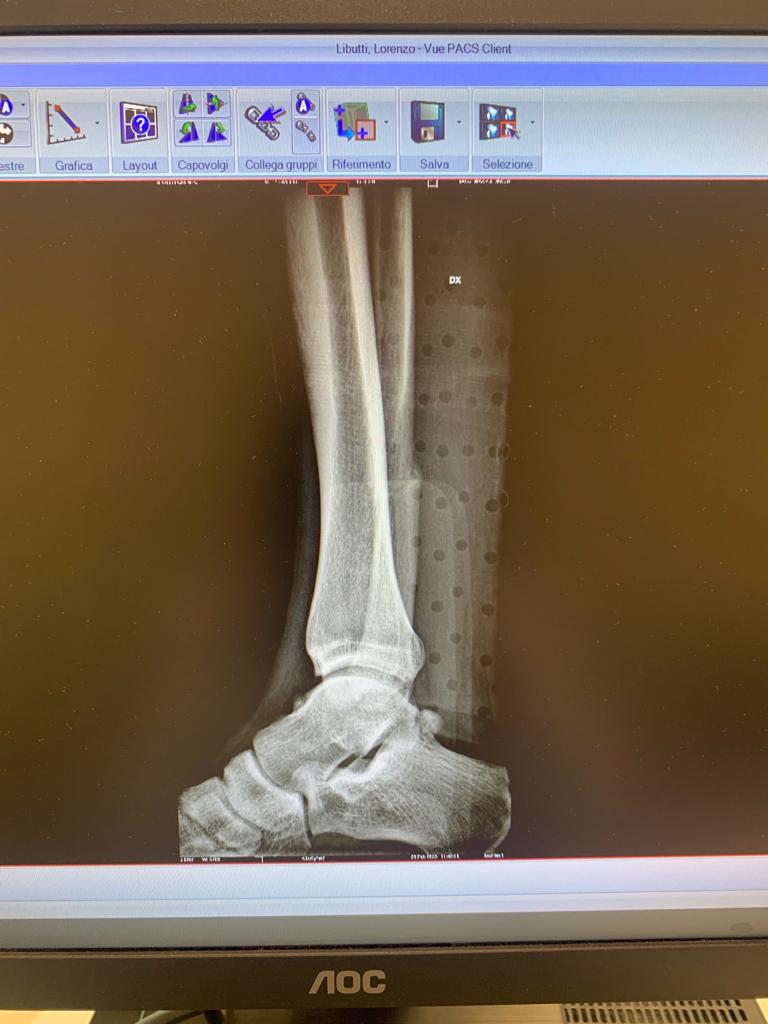

Un infortunio di questo tipo ultimamente è capitato al laterale destro in forza alla Reggiana Lorenzo Libutti. Per Lorenzo la doccia fredda era arrivata sul finire di gennaio al termine di un match dei granata, la diagnosi non lasciava spazio a interpretazioni: frattura del perone! Di seguito potete anche vedere la lastra fatta in ospedale: